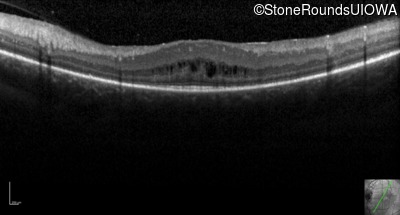

Optical Coherence Tomography - Left - 20/50 -3

Exemplar / OCT Stack